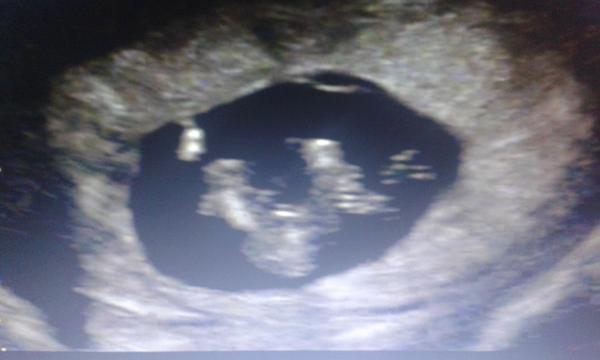

@janulinka03 je to docela podobný..ale nám to tam nějak víc vyčnívá... tak tohle by spíš mohla bý holčička 😀 ??

jasnen no vidis a me rekla doktorka spis chlapecek 🙂 my uz jednoho klucinu mame tak sem chtela holcicku, ale i tak sem moc rada pokud to tak bude! A ja vidim spis chlapecka u tebe, ale urcite to bude naopak 😀 a holcicka 🙂